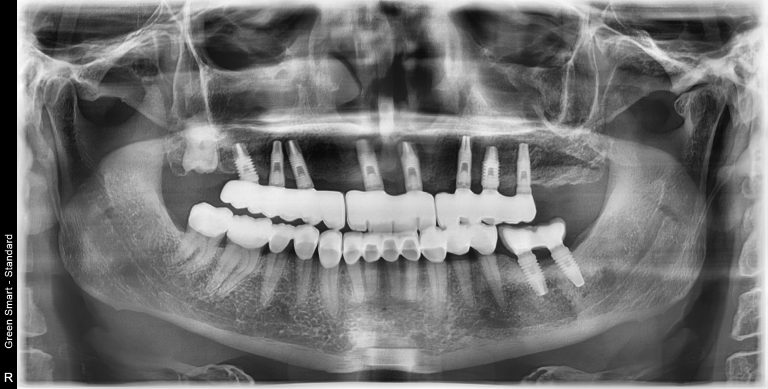

La implantología oral es una especialidad de la odontología que se encarga de la colocación de implantes dentales, dispositivos de titanio que sustituyen la raíz del diente perdido. Estos implantes se integran con el hueso maxilar en un proceso llamado osteointegración, proporcionando una base sólida para la colocación de una corona dental que imita la apariencia y funcionalidad de un diente natural.

1. Evaluación y planificación: Se realiza un estudio detallado con radiografías y escáneres 3D para determinar la viabilidad del tratamiento.

2. Colocación del implante: Bajo anestesia local, el implante se inserta en el hueso maxilar o mandibular.

Si has perdido uno o varios dientes debido a caries, traumatismos o enfermedades periodontales, los implantes dentales pueden ser la mejor alternativa para recuperar tu salud bucal. Este tratamiento es ideal para:

Es importante contar con suficiente cantidad de hueso maxilar para soportar el implante. Si este no es el caso, existen procedimientos complementarios como la regeneración ósea guiada o el injerto de hueso.